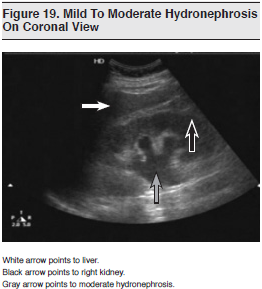

Hydronephrosis is noted on ultrasound when dilatation of the calyces and pelvis result in anechoic areas within the central collecting system. (See Figure 19) Use of color-flow Doppler can help differentiate between renal vasculature and hydronephrosis. When hydronephrosis is noted, it is important to determine whether the obstruction is unilateral or bilateral and, if possible, intrinsic or extrinsic. Hydronephrosis is usually graded as follows: mild (defined by prominent calyces and mild splaying of the renal pelvis), moderate (characterized by a bearclaw appearance), or severe (defined by the presence of cortical thinning). Of note, hydronephrosis may be challenging to appreciate in volume-depleted patients; such patients may need to be hydrated first.